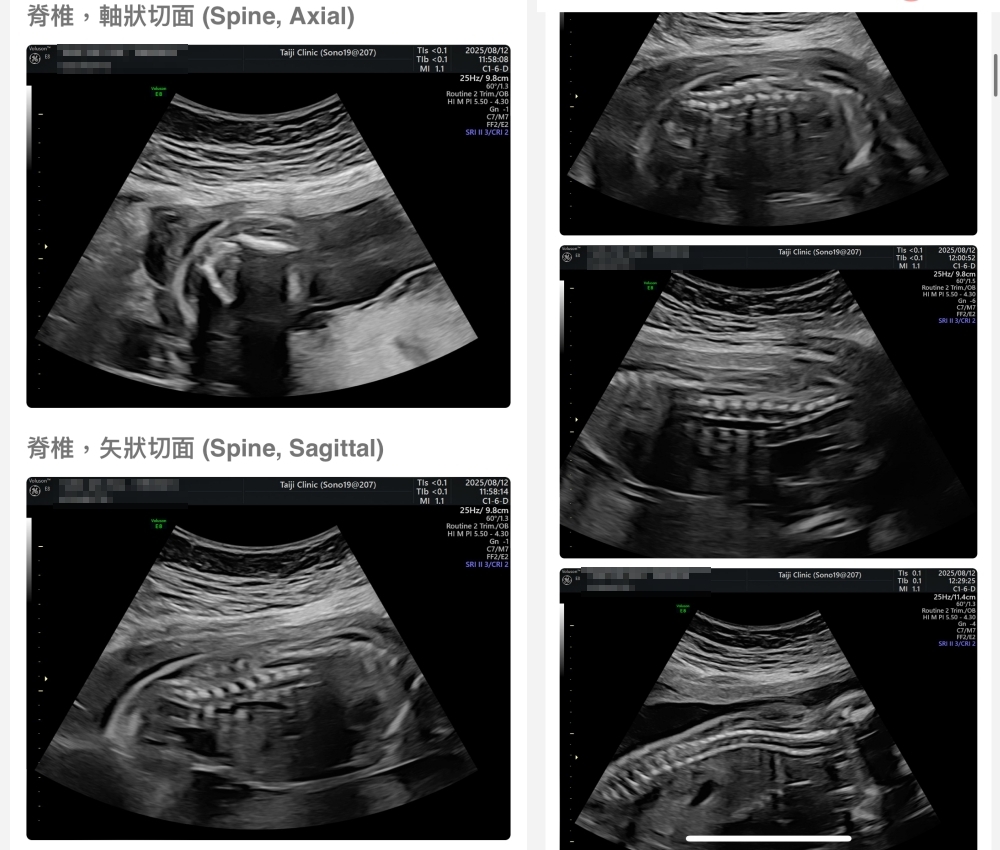

▲離開診所後會收到MAIL,我們14:05離開,大約是16:45收到mail,裡面會有滿滿的超音波照片,紀錄的很詳細!也會提供紙本的報告,可以給日後產檢的醫師做參考👌